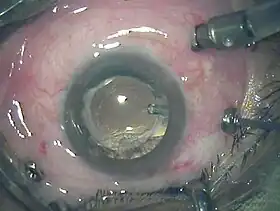

Three port 23-gauge vitrectomy | |